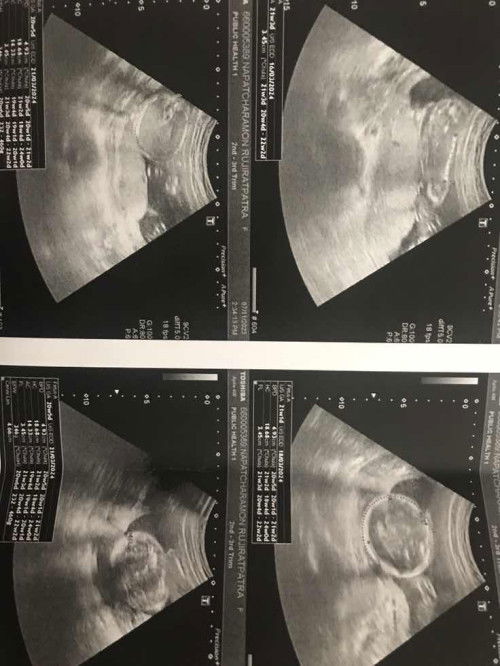

เมื่อวานไปซาวด์มาค่ะ แม่ๆคิดว่า ผญ หรือผู้ชายคะ หมอบอกรายละเอียดน้อยมากค่ะ แม่ๆช่วยกันบอกรายละเอียดเพิ่มเติมได้นะคะ💖🙏🏻#ท้องแรกคะ #ขอบคุณสำหรับคำตอบค่ะ #คุณแม่ๆช่วยแนะนำหน่อยค่ะ